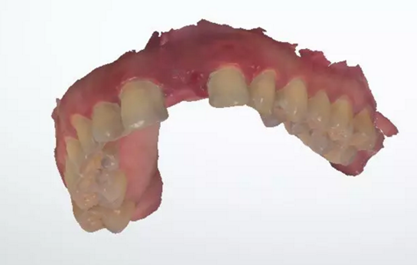

術(shù)前檢查

1.術(shù)前CT

2.術(shù)前植體設(shè)計(jì)

3.術(shù)前導(dǎo)板設(shè)計(jì)